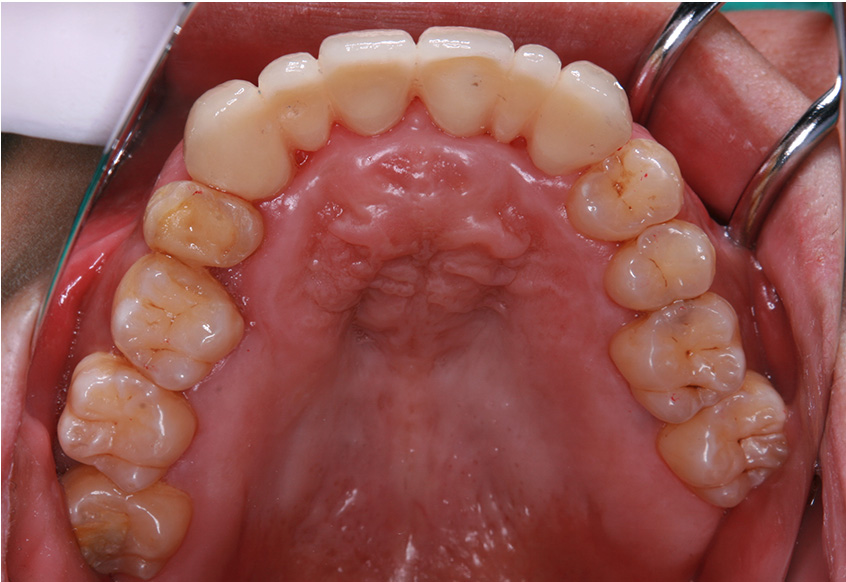

マウスピース(インビザラインGo)による矯正治療(下顎)

術前・術後の比較

治療の概要

| 患者属性 | 30代女性 |

|---|---|

| 主訴 | 下の前歯1本がでているのが気になる |

| 診断 | 下顎歯列不正 |

| 矯正装置 | マウスピース(インビザラインGo) |

| 治療期間 | 4か月(16週) |

| 通院回数 | 初診から合わせて7回の来院 |

| 治療費 | 総額478,500円(初期費用440,000円+診察料4,400円×5ヵ月分+保定装置16,500円/個)費用は税込 |

| 治療内容 | 月1回の歯科医院での治療と日常はマウスピースを常時装着 |

| リスクと副作用 | 矯正治療

|